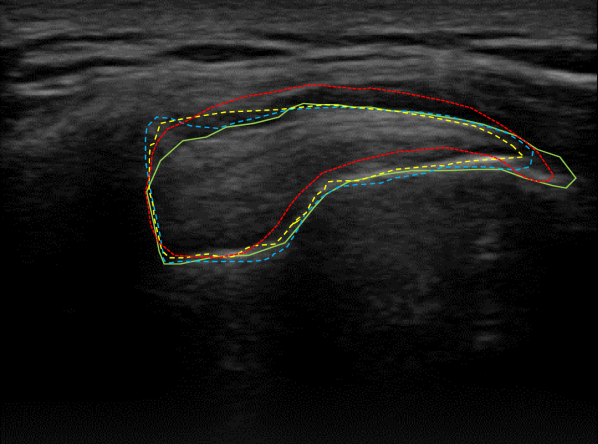

Qualitative performance and advantage of our proposed segmentation method over two different methods are presented in Fig. 8. In this figure, original US images of three cases taken from the SST data-set are shown in the first row and the second row depicts the raw predictions of the NASUNet model. On each image, boundaries of the segmentation maps derived from the ground truth (radiologist annotation), proposed method (NASUNet), DeepLab V3 network (the second best performing method in Table 1), and Active Appearance Model (AAM, the worst-performing method based on Table 1) are drawn with green, blue, yellow, and red colors, respectively. It is evident from Fig. 8 that the delineation by our method is closer to the ground truth annotation in comparison with other methods, which indicates the power and efficiency of NASUNet in SST boundary detection. In all of the subsequent tendinopathy recognition experiments, resulting segmentations from the best performing model (NASUNet) are utilized.

Figure 8: Visualizing the SST boundaries resulted from different segmentation methods for three different cases in the first row. Boundaries of ground truth, proposed NASUNet model, DeepLab v3 network, and AAM method are overlaid on their related images with green, blue, yellow, and red colors, respectively. The second row illustrates the raw segmentation prediction maps from NASUNet.